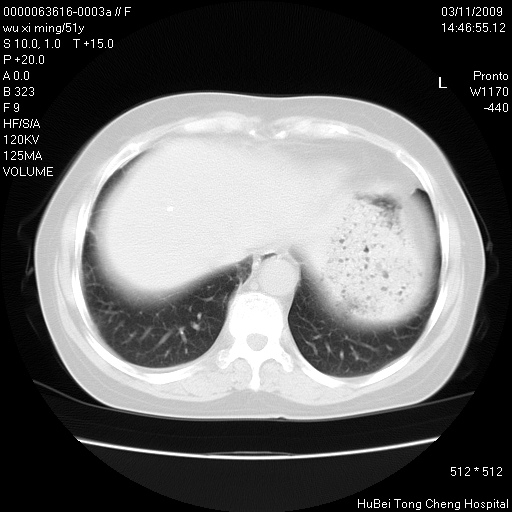

患者 女,51岁。因“胆囊炎,胆囊结石”,行常规术前胸部x线检查发现:右上肺结节病灶,建议行进一步检查。患者无咳嗽、咳痰及咯血等呼吸道症状,近期出现背部疼痛不适。

胸部ct轴位平扫(层厚10mm,螺距1.5,重建间隔10mm;部分层面:层厚3mm,螺距1.0,重建间隔3mm),图像如下:

右肺周围型肺癌伴肺内转移信胸椎转移

支持--右肺周围型肺癌---胸椎转移

集束征,胸膜牽拉征,毛刺,淺分葉高度提示ca.

右肺周围型肺癌伴肺内转移及胸椎转移。已无手术机会。